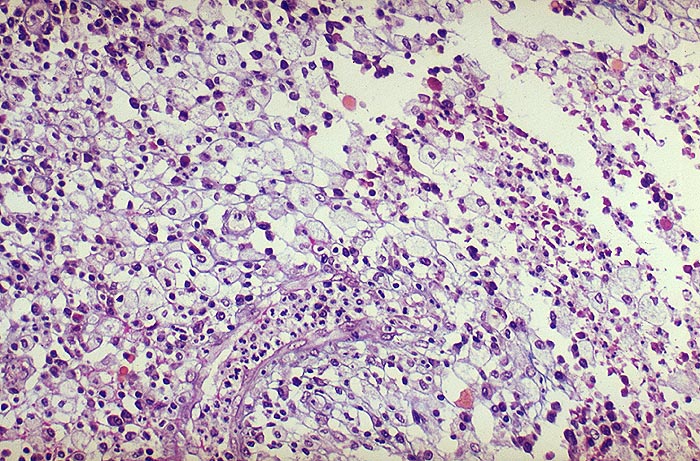

Typische Schaumzellen (Xanthomzellen) aus dem Granulationsgewebewall. Zwischen den Schaumzellen auch Lymphozyten-Plasmazellen sowie gelapptkernige Leukozyten.

Stets einseitige Pyelonephritis mit typischer Trias:

1. Obstruktion der ableitenden Harnwege zumeist durch Phosphatsteine

2. Coli oder Proteusinfekt

3. Störung der Leukozytenfunktion. Kommen tuberkuloide Granulome vor, wird fälschlicherweise oft eine Tuberkulose diagnostiziert. Bei Tuberkulose aber nie Schaumzellen. Die Malakoplakie der Niere ist im Gegensatz zur xanthogranulomatösen Pyelonephritis stets beidseitig.